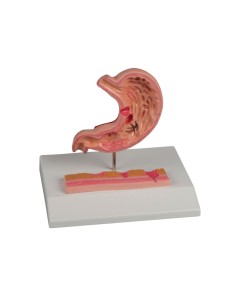

3B Modèle scientifique et anatomique : Pathologies de l'intestin K55

Indispensables aux étudiants comme aux professionnels, nos modèles anatomiques sont des outils pédagogiques qui permettent d'observer les structures anatomiques avec précision, en évitant les dissections ou les études invasives. Ils sont également utiles pour expliquer les pathologies aux patients, ce qui rend la communication plus efficace et permet de gagner un temps précieux.